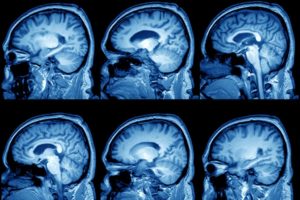

На сегодняшний день основными методами диагностики и последующего прогноза данной болезни являются МРТ (магнитно-резонансная томография) и КТ.

Полученная томограмма показывает состояние всех составляющих мозга (эпифиза, мозжечка, гипофиза, нервных ганглий и других частей).

С ее помощью можно увидеть место расположения перивентрикулярного глиозного очага и атрофических рубцовых следов внутри головного мозга без вскрытия черепной коробки, оценить их форму, размеры и интраселлярный рост.

Кроме того, данные способы обследования позволяют сделать дифференциальную диагностику промежуточного состояния между доброкачественной кистой и злокачественной опухолью. После внутривенного введения специального контрастного вещества его продукт накапливается в опухолевых тканях, а киста при этом не становится контрастной.

- КТ и МРТ головного мозга — на данный момент самые достоверные методы обследования, позволяющие не только обнаружить кисту и определить её точную локализацию, но и узнать её гистологическую структуру. Для выявления такой патологии, как киста головного мозга, чаще используют МРТ, так как этот метод более чувствителен к мягким тканям и не даёт «слепых зон» в отличие от КТ. Имеется в виду, что при использовании КТ плохо визуализируются структуры мозга, расположенные в задней черепной ямке. Если всё-таки нет возможности провести МР исследование, то выполняют КТ с внутривенным усилением, то есть вводится контрастное вещество;